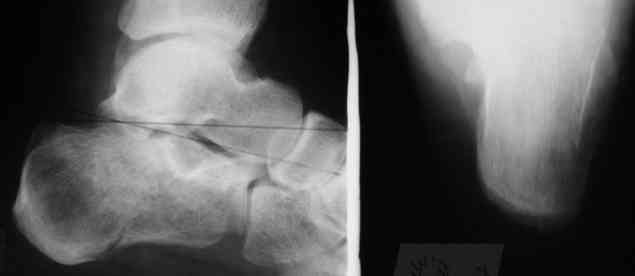

Уважаемые коллеги! Пришел на консультацию больной - "растяжение связок левого голеностопного сустава" полтора месяца назад, поскольку был в морях, на ногу не наступал. Снимки и КТ - в приложении.

Как бы кто лечил с учетом времени после травмы - 52 дня? Человек физического труда. Социальные запросы самого больного высокие, плюс медкомиссии перед рейсами - с хромотой нельзя!

Целесообразно Вашему пациенту выполнить подтаранный компрессионный расклинивающий артродез с использованием канюлированных винтов.

52 дня - неудобный срок, особенно учитывая недостаточную нагрузку ноги в плавании. Я обычно пациентам в такой ситуации назначаю препараты кальция и дозированную нагрузку, через 1-1,5 месяца после - оперируем. Операция показана для восстановления оси и высоты пяточной кости, устранения грушевидного расширения ее и вальгусного отклонения,устранения болевого и посттромботического синдромов. Тему лечения осложненных переломов пяточной кости в поздние сроки не освещал в известной Вам монографии сознательно: это одна из глав диссертации моего ученика С.М.Платонова.